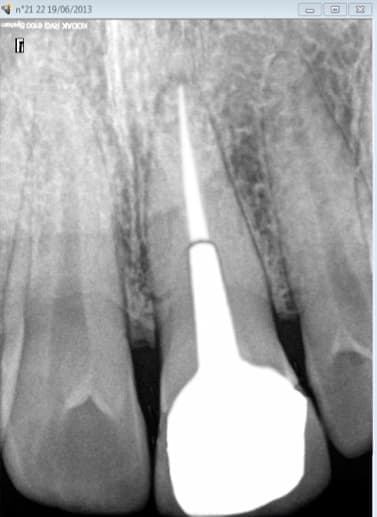

chicot29

28/02/2016 à 00h36

celle là est pas mal mais en sens inverse.De la pate avant mais plus après pose de l'ic coiffe dans le palatin.

le patient s'en est aperçu 5 ans après suite à un signe d'appel.

Ce patient c'est moi. -)

Capteur VS plaque il n'y a pas photo. -)